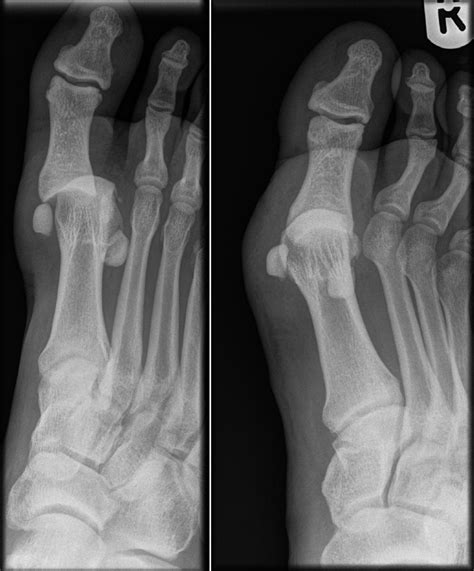

Turf toe is technically known as a metatarsophalangeal (MTP) joint sprain. It occurs when the big toe is forcibly bent upward, often against a rigid surface like artificial turf, damaging the soft tissues that stabilize the joint. This tissue complex, known as the plantar plate, is crucial for pushing off during walking, running, and jumping.

• Grade 3: A complete tear of the ligament, often involving damage to the joint capsule and surrounding cartilage, which frequently necessitates Turf Toe Surgery.

• Cartilage Damage: If the injury has caused loose bone fragments or damaged articular cartilage within the joint.

• Presence of Hallux Valgus or Deformity: If the injury has caused the big toe to deviate, affecting long-term gait and biomechanics.